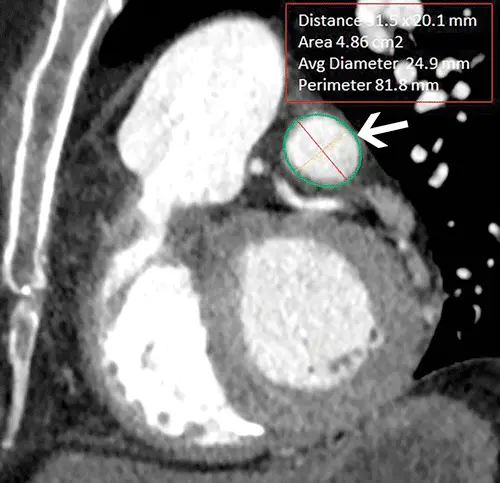

• Caption: En-face-view CT image shows the cross-sectional view of the landing zone (arrow), where the maximum diameter, minimum diameter, and perimeter are measured.